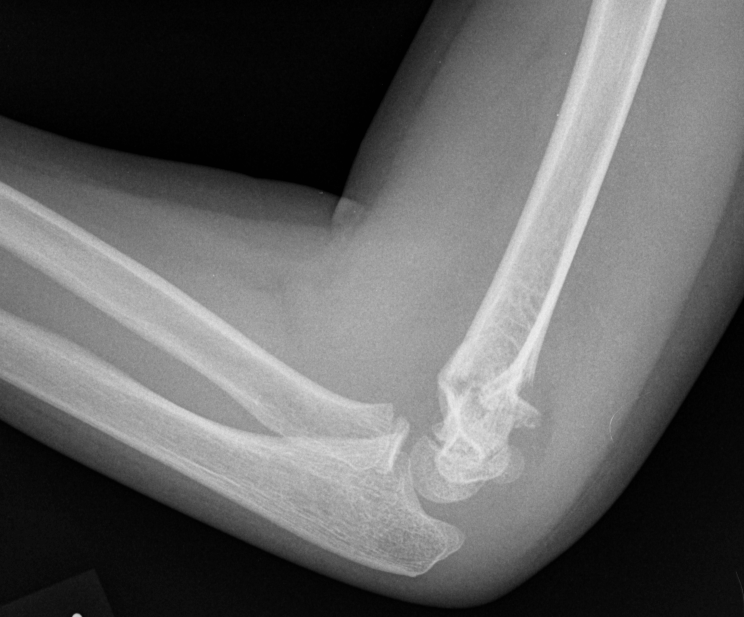

3. Supracondylar fracture of elbow